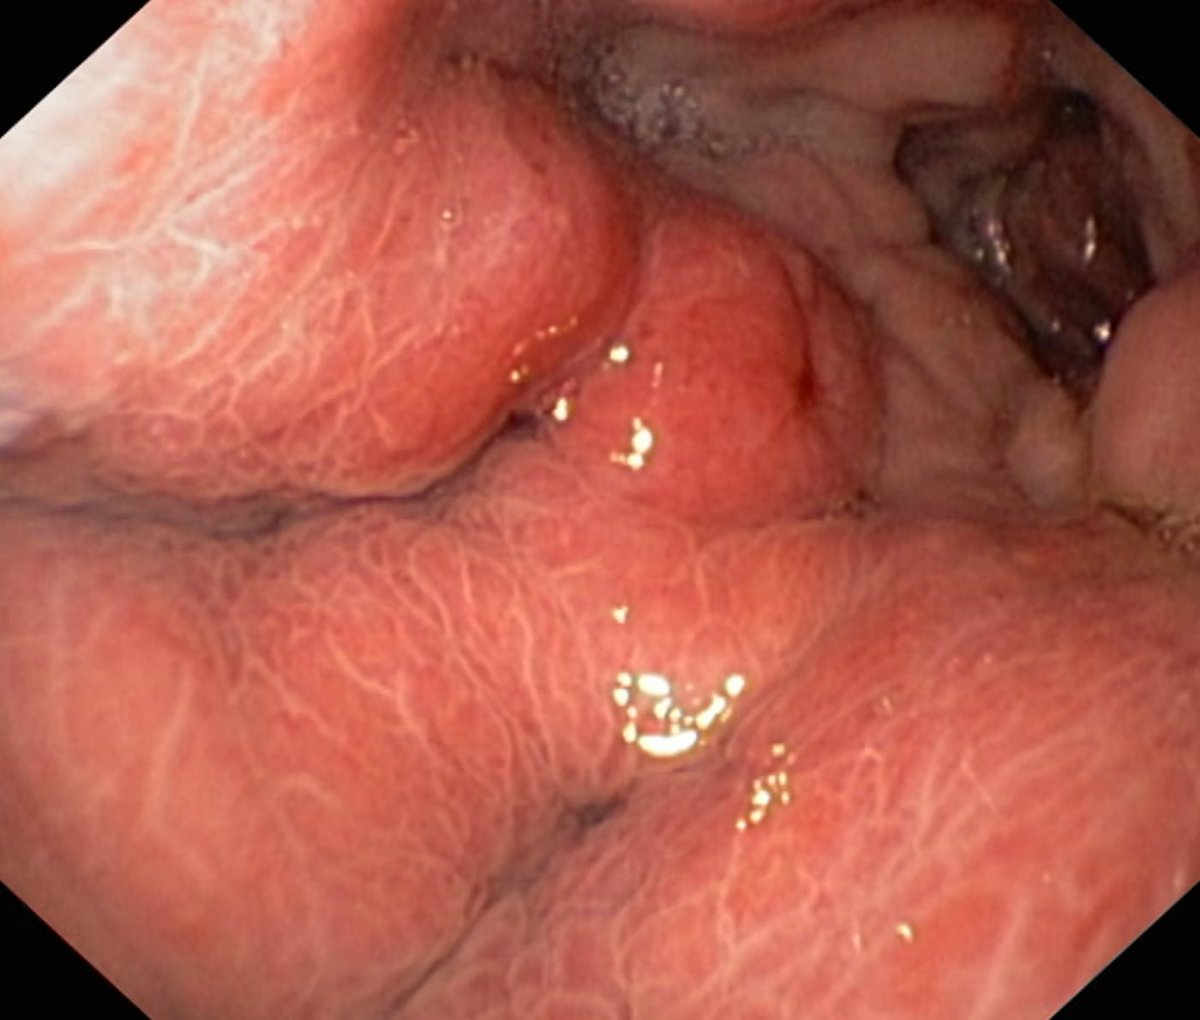

Missed out on the🔥#ScopingSundays discussion this past weekend on “Management of Esophageal Varices 🩸”

Check out the #ScopingSummary from the interactive discussion led by @AdvaniRashmiMD, @gioroldanc & @RahulKarnaMD!

Time to get ready to manage #EsophagealVarices 🩸!

@drkeithsiau Esophageal Stent sometime can be used for active bleeding post banding ulcerative esophagus varicies when other other options limited